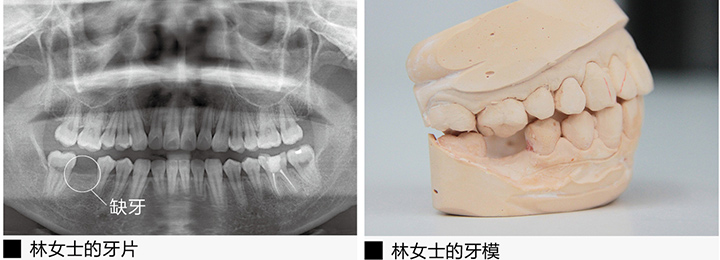

林女士的“六龄齿”也就是第一恒磨牙,缺失了整整5年了,从一开始的蛀牙没有及时补起来,到后来不断地塞牙发炎,蛀洞变大,到最后整颗牙掉落,林女士没少受罪。对于看牙,她害怕得很。补牙,拔牙都怕,更别说在那么窄小的牙槽骨里植入种植体,进行种植牙修复了。

可是,一想到自己年纪还轻,嘴里的其他牙齿也多少有龋坏,缺损等各种问题,如果这颗牙再不修复,不仅增加了其他牙齿的咀嚼负担,缺牙边上的牙齿也会因为没有依傍而倾斜,林女士想要用种植牙让自己的“六龄齿”重生起来。